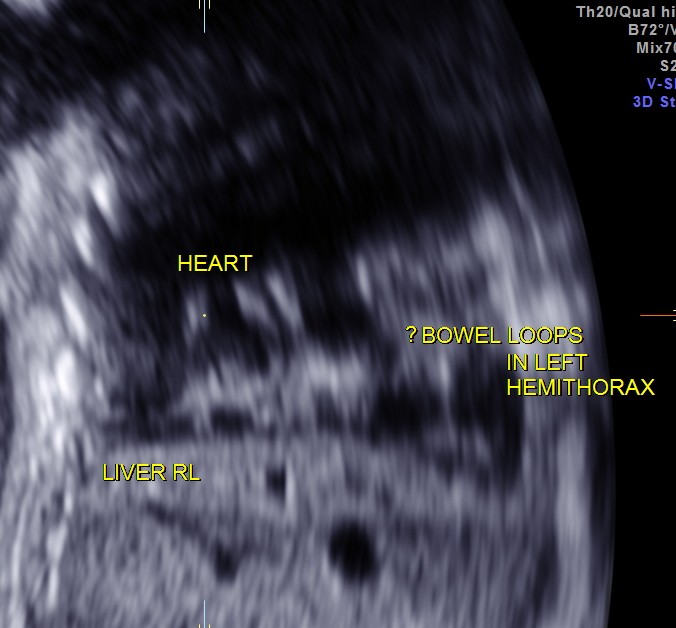

This was a 23 year old primi gravida without history of consanguinity was sent for anomaly scan at 33 weeks of gestation. Earlier two scans had not detected any anomaly at another centre.

The heart was seen in the right side of thorax . The left hemithorax showed the stomach bubble and bowel loops suggestive of Congenital Diaphragmatic Hernia .